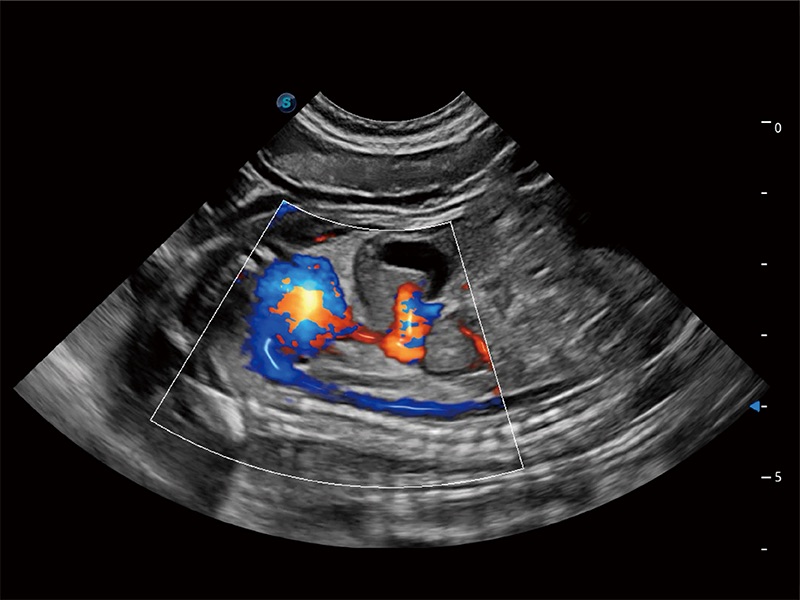

ProPet 80 配备了丰富的心脏探头群、先进的成像技术和专业的心脏测量工具,可帮助动物医生为不同体型和生理结构的动物提供心脏和心肌功能的全面评估。

通过360度任意调节3条M型取样线,在同一心动周期上观察心脏不同位置的运动曲线,得到准确的心功能测量数据,有效评估心肌运动及左心室功能。